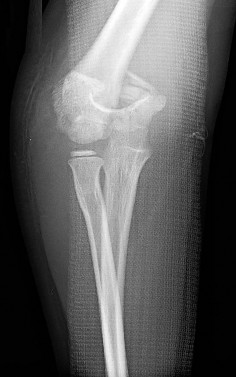

A 5-year-old boy presents with an extension-type Gartland III supracondylar humerus fracture after a fall.

On examination, his hand is well-perfused (pink) with brisk capillary refill, but the radial pulse is absent. What is the most appropriate initial management?